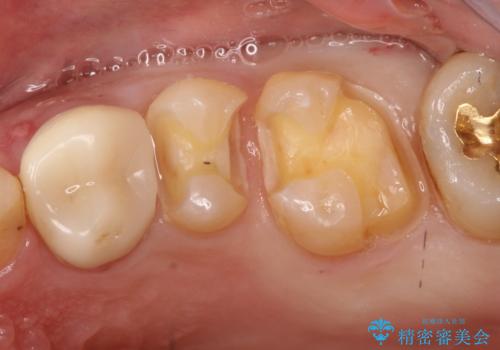

- 定期健診にて虫歯が見つかった患者さんです。他院で保険治療(CR、プラスチック)したところとまだ処置されていないところが虫歯になっていました。

セラミックインレーで治療しました。

以前保険治療で治したところが再び虫歯になっていました。保険治療で使用される材料は主にプラスチックなので必ず劣化がおきます。再治療のリスクを減らすために、セラッミックインレーで治療を行いました。セラミックインレーには劣化がほとんどありません。当院ではシリコンで型取りを行っているので、適合が良い被せものが出来き再治療のリスクを減らすことが出来ます。